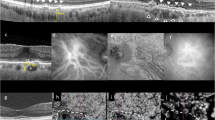

Ultrastructural analysis of the rodent choroidal innervation was performed using transmission electron microscopy (TEM) and Serial Block Face—Scanning Electron Microscopy (SBF-SEM) (Fig. 3). It shows that large choroidal nerves contain both large, myelinated fibres and numerous groups of non-myelinated fibres (Fig. 3a, c, d), together with adjacent myelinating Schwann cells (mSC) and non-myelinating Schwann cells (nmSC). Outside of ciliary nerves, the non-myelinated fibres that fill the intervascular space extend anteriorly to innervate the choriocapillaris (Fig. 3a, b) as shown by SBF-SEM, which allows the tracking and the 3D reconstruction of these fibres (Fig. 3b—Supplementary file 1), confirming our immunostaining findings on sections (Fig. 1e, f).

Ultrastructure of mouse choroidal innervation by SBF-SEM and TEM. a A single section of the mouse choroid from a volume acquired by SBF-SEM, showing a large choroidal nerve (purple), choroidal nerve fibres (magenta) and the choriocapillaris (CC, in red). Other small fibres are visible (arrows) as well as pigments from melanocytes (white) and large vessels (dark). b 3D reconstruction of the SBF-SEM volume presented in A, with the myelin of the large nerve (purple), the choroidal nerve fibre (magenta) and the choriocapillaris (red) segmented. The reconstruction reveals the ultrastructural organisation of the choroidal innervation, with a clear innervation of large vessels (arrow) and CC/RPE (star). c, d Transmission electron microscopy (TEM) analysis of a large choroidal nerve after osmium contrasting. The large nerve is composed by large, myelinated fibres (mf) nearby myelinating Schwann cells (mSC) and group of non-myelinated fibres (nmf) where non-myelinating Schwann cells (nmSC) are visible. N: myelinated Schwann cell nucleus

Semithin and ultrastructural analysis of P1.hMR and WT littermate mice choroid and choroidal nerves. a–c Semithin transversal eye section of WT littermate mice. The photoreceptor outer segments are aligned and the choriocapillaris are clearly noticeable between large choroidal artery and RPE (a). RPE pigments are concentrated and well spread toward the apical pole of the cells (a inset and b). Choroidal nerve displays healthy structure with normal myelin organisation (c). (d–g) Semithin transversal eye section of transgenic P1.hMR mice where several features of pachychoroid are observed. Dilated vessels in direct contact with Bruch membrane and effacement of the overlying choriocapillaris (“pachyvessel”) (d, left inset) associated with irregular pigment distribution in the RPE (d, right inset). Dilated veins (e, black double arrows), with focal area of elongated undigested photoreceptor outer segments (f, black arrows) and subretinal deposits associated with abnormal RPE/photoreceptor outer segment interface (f, white arrows). These are accompanied by irregular pigment distribution in the RPE and subretinal migration of RPE cells (f, inset). These features resemble pachychoroid epitheliopathy described in humans. In P1.hMR, enlarged nerves with irregular myelin shedding (white arrows) and disorganisation were observed (g). These neural abnormalities were more obvious in electron microscopy observations. TEM of WT littermate (h, i) and transgenic P1.hMR mice (k, l) choroidal nerves. Transgenic mice display signs of neuropathy, including myelin abnormalities (k, white arrows), increased number of large mitochondria (l, white arrows) and loss of organisation and vacuolization of the nerve. SBF-SEM sections of a choroidal nerve in a WT littermate (j, purple area) or in a transgenic mouse (m, green area), and the corresponding 3D segmentation of the myelin (n). Myelin abnormalities in transgenic animals are clearly apparent, including large variation of the G-ratio

Similar to our observations in rodents, ultrastructural analysis by TEM shows large nerves formed by myelinated and unmyelinated fibres, together with myelinated and non-myelinated Schwann cells (Fig. 4t). Numerous non-myelinated fibres are in close contact with all vessel types including arteries, veins, and choriocapillaris (Fig. 4u, v).

hMR overexpression is associated with pachychoroid-like phenotype and with choroidal neuropathy

In transgenic mice overexpressing hMR, several features of chorioretinopathy are observed in semithin sections, in different areas as compared to WT littermates (Fig. 5). Vascular abnormalities include dilated veins with focal area in direct contact with the Bruch membrane, leading to an effacement of the choriocapillaris (Fig. 5d), similar to pachyvessels described in humans in spectral domain optical coherence tomography. Abnormal melanosome organisation is found in RPE cells with irregular distribution and area of aggregation (Fig. 5d–f). The large choroidal nerves show signs of neuropathy, such as fibres enlargement and myelin disorganisation (Fig. 5g).

TEM observations in transgenic animals confirm clear signs of neuropathy including myelin and fibres disorganisation as well as vacuolization and mitochondrial abnormalities. Myelin abnormalities include local demyelination and important variations in the ratio between fibres thickness and myelin sheet thickness, which are not present in littermates (Fig. 5h, i, k, l). Large fibres also lost their circular shapes and are often found flattened (Fig. 5k), with vacuolization and unmyelinated disorganised fibres. Finally, TEM analysis of transgenic mice also showed an increased number of large and osmium-labelled mitochondria inside both myelinated and unmyelinated fibres (Fig. 5l), constituting a characteristic sign of neuropathy. SBF-SEM acquisitions were used to visualise in 3D the myelin organisation in large choroidal nerves of transgenic and littermate animals (Fig. 5j, m, n). These reconstructions were consistent with the previous observations in TEM, confirming the myelin disorganizations and irregularity along the nerve in P1.hMR mice (Fig. 5n). Typical ultrastructural signs of choroidal neuropathy result from mineralocorticoid receptor pathway overactivation in transgenic mice.

Using TEM and SBF-SEM, we show herein typical signs of choroidal neuropathy in P1.hMR mice including myelin abnormalities, accumulation and enlargement of mitochondria and loss of organisation and vacuolization of choroidal nerves. Thus, hMR overexpression in mouse causes a pachychoroid-like phenotype and a choroidal neuropathy. Since, the ChNS regulates all choroidal vessels, macrophages and possibly RPE cell functions, choroidal neuropathy secondary to MR overactivation could be the unifying link between all pathological signs.